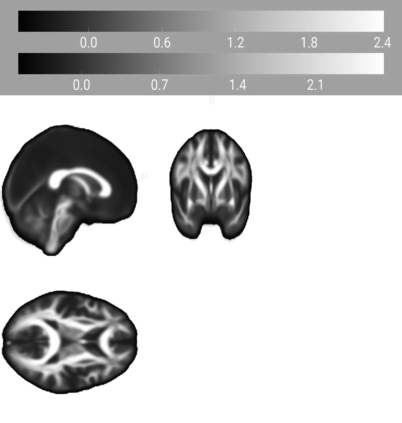

Our knowledge of the organisation of the human brain at the population-level is yet to translate into power to predict functional differences at the individual-level, limiting clinical applications, and casting doubt on the generalisability of inferred mechanisms. It remains unknown whether the difficulty arises from the absence of individuating biological patterns within the brain, or from limited power to access them with the models and compute at our disposal. Here we comprehensively investigate the resolvability of such patterns with data and compute at unprecedented scale. Across 23 810 unique participants from UK Biobank, we systematically evaluate the predictability of 25 individual biological characteristics, from all available combinations of structural and functional neuroimaging data. Over 4526 GPU hours of computation, we train, optimize, and evaluate out-of-sample 700 individual predictive models, including fully-connected feed-forward neural networks of demographic, psychological, serological, chronic disease, and functional connectivity characteristics, and both uni- and multi-modal 3D convolutional neural network models of macro- and micro-structural brain imaging. We find a marked discrepancy between the high predictability of sex (balanced accuracy 99.7%), age (mean absolute error 2.048 years, R2 0.859), and weight (mean absolute error 2.609Kg, R2 0.625), for which we set new state-of-the-art performance, and the surprisingly low predictability of other characteristics. Neither structural nor functional imaging predicted psychology better than the coincidence of chronic disease (p<0.05). Serology predicted chronic disease (p<0.05) and was best predicted by it (p<0.001), followed by structural neuroimaging (p<0.05). Our findings suggest either more informative imaging or more powerful models are needed to decipher individual level characteristics from the human brain.